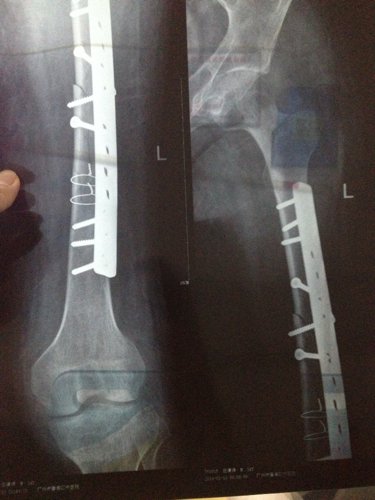

你好医生!左腿原来有小儿麻痹证,就在上个月11号不小心跌倒骨折13号做手术加钢板!现在在家休养 现 你好医生!左腿原来有小儿麻痹证,就在上个月11号不小心跌倒骨折13号做手术加钢板!现在在家休养。现在腰很痛?是怎么回事,有过性生活。现在简单吃两种药?请问医生像我这种情况会不会很难恢复原来那样?是不是还要吃些什么?还有要不要外敷些什么?还要腰很痛怎么办,谢谢! 点击展开 匿名用户 2014-04-08 09:50 为您推荐: 其他回答 病情分析: 你好,考虑是恢复期间的应急反应。 指导意见: 可以多食瘦肉、鱼、鸡蛋、牛奶、豆类食品以及新鲜蔬菜、水果等,注意逐渐恢复锻炼。 独水凡_xjeq 2014-04-08 10:51 相关问题 你好、请问:左小腿骨折做手术取钢板后可以同房吗?同房有影响吗?还是需要等的话要多久? 骨博士你好,我膝盖上面一点点骨折了,已经八个月了能取出钢板了吗 骑电动车把左股骨颈摔骨折了,而且左腿是小儿麻痹,女,年龄五十四岁,在家静养能康复吗?有什么好办法吗

你好医生!左腿原来有小儿麻痹证,就在上个月11号不小心跌倒骨折13号做手术加钢板!现在在家休养。现在腰很痛?是怎么回事,有过性生活。现在简单吃两种药?请问医生像我这种情况会不会很难恢复原来那样?是不是还要吃些什么?还有要不要外敷些什么?还要腰很痛怎么办,谢谢!